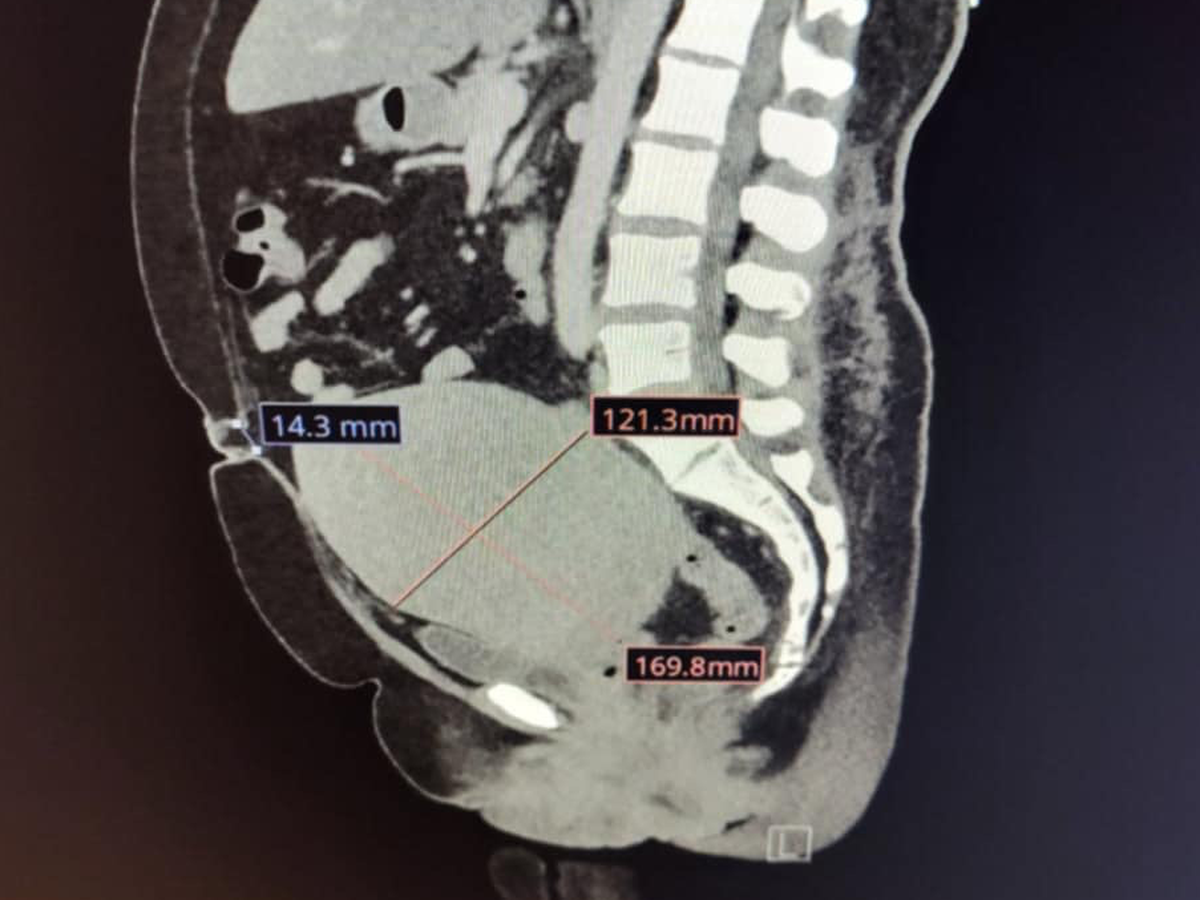

Hello everyone, my name is Melissa and I am in desperate need of a hysterectomy and an umbilical hernia repair surgery. I need to have both surgeries at the same time. My uterus is the size of a basketball and needs to be removed because it’s pressing against all my vital organs and main vein.